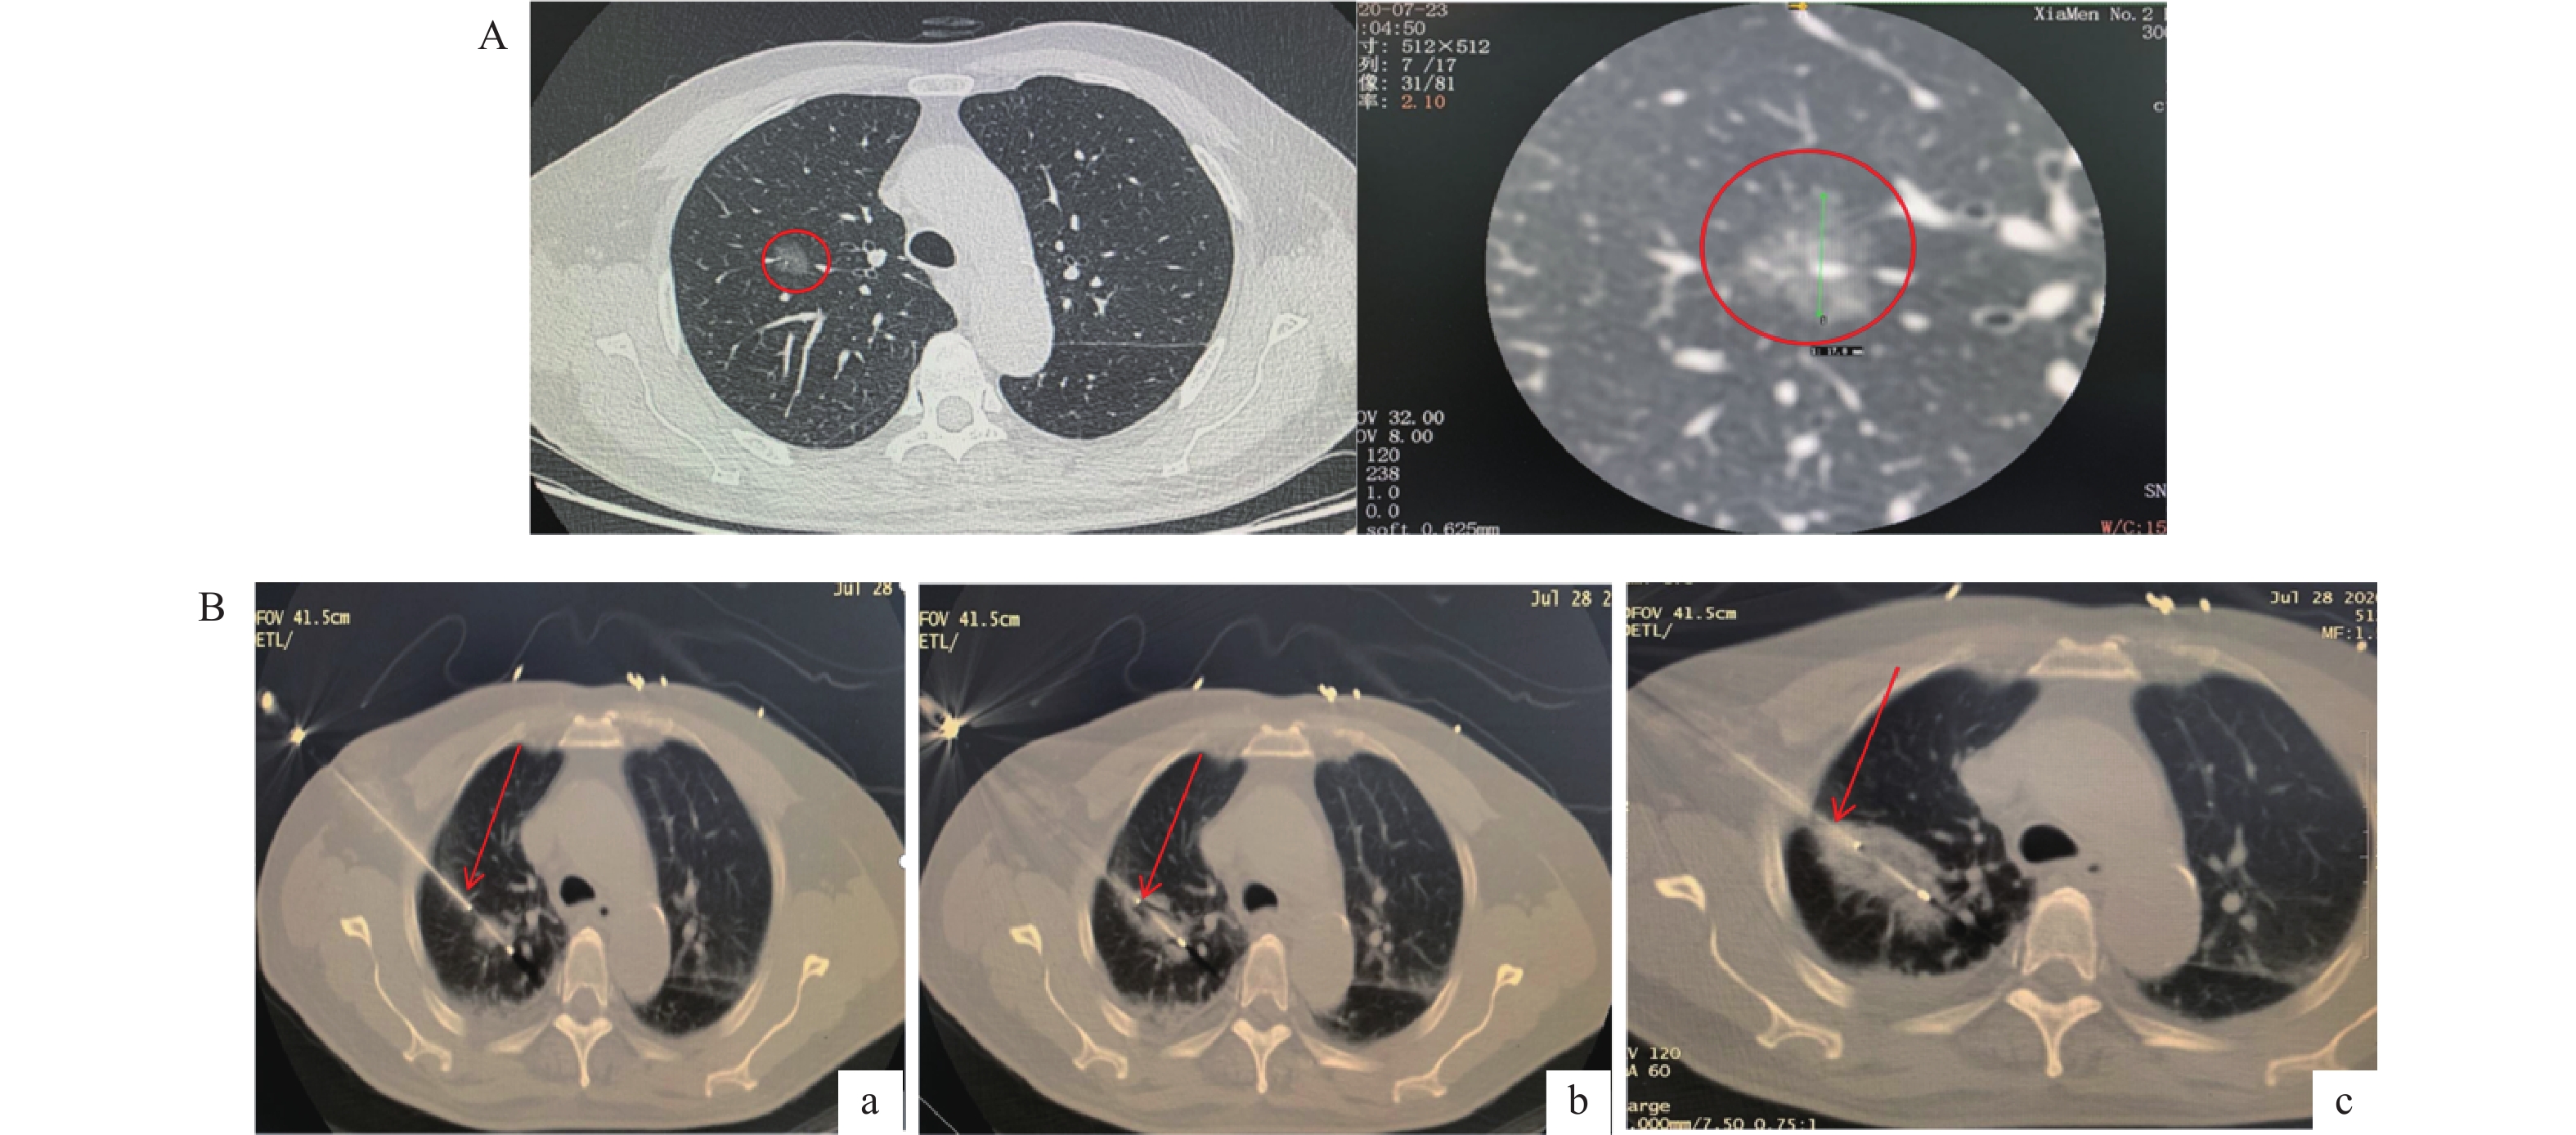

目的   分析高危肺结节微波消融(microwave ablation,MWA)术前后血管生成素-2(angiopoietin-2,Ang-2)水平变化及其对术后复发的影响。   方法   纳入2019年12月至2021年12月贵州航天医院94例高危肺结节患者,分为复发组(n = 30)和未复发组(n = 64)。比较两组患者临床资料。通过Pearman相关性分析治疗前Ang-2水平与CT参数的关联。通过Logistic回归模型、限制性立方样条及阈值效应、受试者工作特征(receiver operating characteristic,ROC)曲线分析治疗前Ang-2水平与术后复发的关系。采用Kaplan-Meier生存曲线分析不同水平Ang-2患者总生存期差异。利用COX回归模型分析影响患者生存期的因素。   结果   与同组治疗前相比两组Ang-2水平均明显降低,差异有统计学意义(P < 0.05)。Pearman相关性分析显示,治疗前Ang-2与BF、BV、PS、MTT均呈正相关。Ang-2水平与术后复发存在独立相关性。ROC结果显示,治疗前Ang-2对术后复发具有一定的预测价值(曲线下面积为0.789)。限制性立方样条分析显示,治疗前Ang-2与术后复发呈非线性剂量-反应关系(P < 0.05)。阈值效应分析显示,Ang-2影响复发的拐点为1905.41  pg/mL。生存分析显示,Ang-2<1905.41  pg/mL组患者中位总生存期长于Ang-2≥1905.41  pg/mL组(P = 0.039)。且Ang-2≥1905.41  pg/mL是影响患者生存期的独立因素。   结论   高危肺结节患者微波消融术治疗后Ang-2水平明显降低,治疗前Ang-2对术后复发具有一定预测价值。